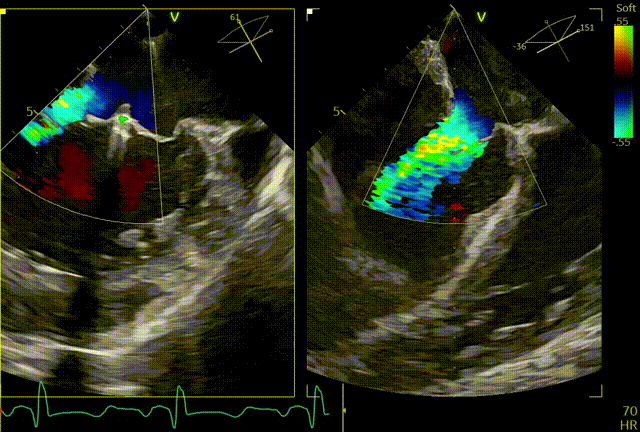

3D

3D带彩

术前肺静脉频谱

3区gap

术前左房压